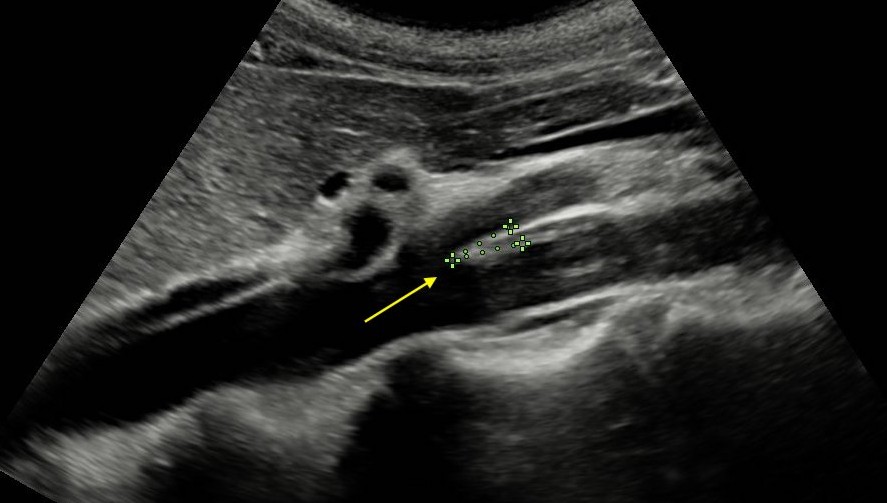

Ecografía clínica: La ecografía abdominal realizada en consulta mostró riñones normotróficos, sin litiasis ni hidronefrosis. La vía urinaria y el parénquima renal eran normales. Al evaluar grandes vasos abdominales se observó dilatación proximal de la vena renal izquierda y estrechamiento marcado en el ángulo formado entre la arteria mesentérica superior y la aorta, hallazgo sugestivo de síndrome de cascanueces. No se identificaron alteraciones anexiales ni signos de diverticulitis.

Dolor abdominal secundario a congestión venosa renal por síndrome de Cascanueces. Se descartaron cólico nefrítico, pielonefritis, patología diverticular, enfermedad inflamatoria intestinal y procesos ginecológicos agudos.